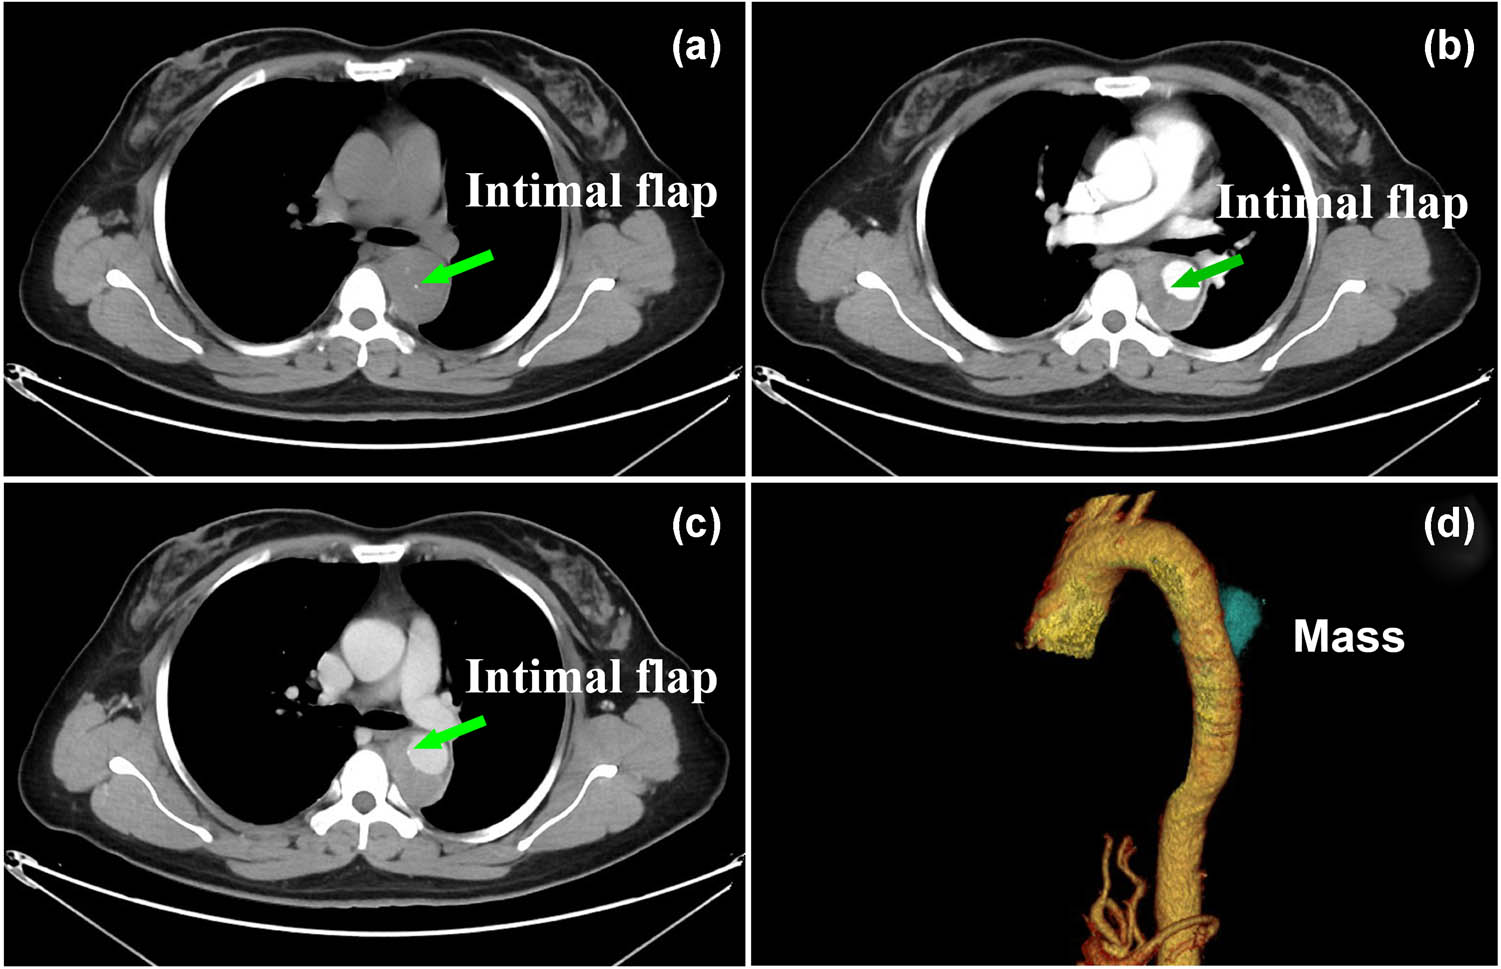

A 49-year-old woman visited the emergency room for acute chest pain radiating to the back. She had known hypertension: the blood pressure in the left upper limb, right upper limb, left lower limb, and right lower limb was 210/65, 218/60, 176/90, and 175/90 mm Hg, respectively. The D-dimer level was normal at initial admission. An electrocardiogram showed a normal sinus rhythm. Considering that the patient had typical clinical symptoms of acute chest pain radiating to the back, with asymmetry of limb blood pressures, and a normal D-dimer level and electrocardiogram, the diagnosis of IMH was suspected. Chest nonenhanced computed tomography (CT) was performed, which showed crescent-shaped thickening of the thoracic aorta wall with the same attenuation as that of the lumen and linear calcification ingression (Figure 1a). Computed tomography angiography (CTA) revealed an intimal flap and expanded false lumen with slight enhancement (Figure 1b–d). Digital subtraction angiography showed mild stenosis in the thoracic aortic lesion without an obvious intimal flap (Figure 2a). Based on both the clinical symptoms and diagnostic test results, only thoracic IMH was considered by both radiologists and cardiothoracic surgeons; hence, thoracic endovascular aortic repair and not surgery was considered at that time. Then, an endovascular stent (30 mm × 200 mm, Medtronic) was implanted into the patient. Completion angiography demonstrated that the thoracic aorta and branches were patent, with no obvious endoleak or extravasation (Figure 2b). The prevalence of acute chest pain radiating to the back decreased after treatment, and the patient recovered well and was discharged home.

Axial nonenhanced CT images (a) showing a crescent-shaped thickening of aortic wall with the same attenuation as that of the lumen and intimal flap. CTA (c and d) showing an intimal flap and expanded false lumen with slight enhancement, and correspond reconstructed image (d) showing a mass-like false lumen, which was interpreted by radiologists as IMH.

Primary aortic intimal sarcoma can be diagnosed only by postoperative histopathology and immunohistochemical markers, while its preoperative diagnosis is challenging because of various clinical manifestations and no specific imaging features. Based on previous case reports [2,3,4,5,6,7], aortic intimal sarcoma often presents with features similar to those of atherosclerotic plaque and thrombus on CT images, and the most frequently reported clinical symptoms are caused by embolic events. In contrast to prior studies, acute chest and back pain with asymmetry of limb blood pressures and an expanded false lumen with an intimal flap were the only features observed on CT images. Thus, as these features were similar to those of IMH, this led to the confident diagnosis of “mimicking IMH.” An episode of acute chest and back pains might be explained by micro-calcification/micro-hemorrhage of the tumor, which showed as a hyperintense foci at the center of the aorta on the non-contrast CT (Figure 1a and b) and that was interpreted by radiologists as “intimal flap.”